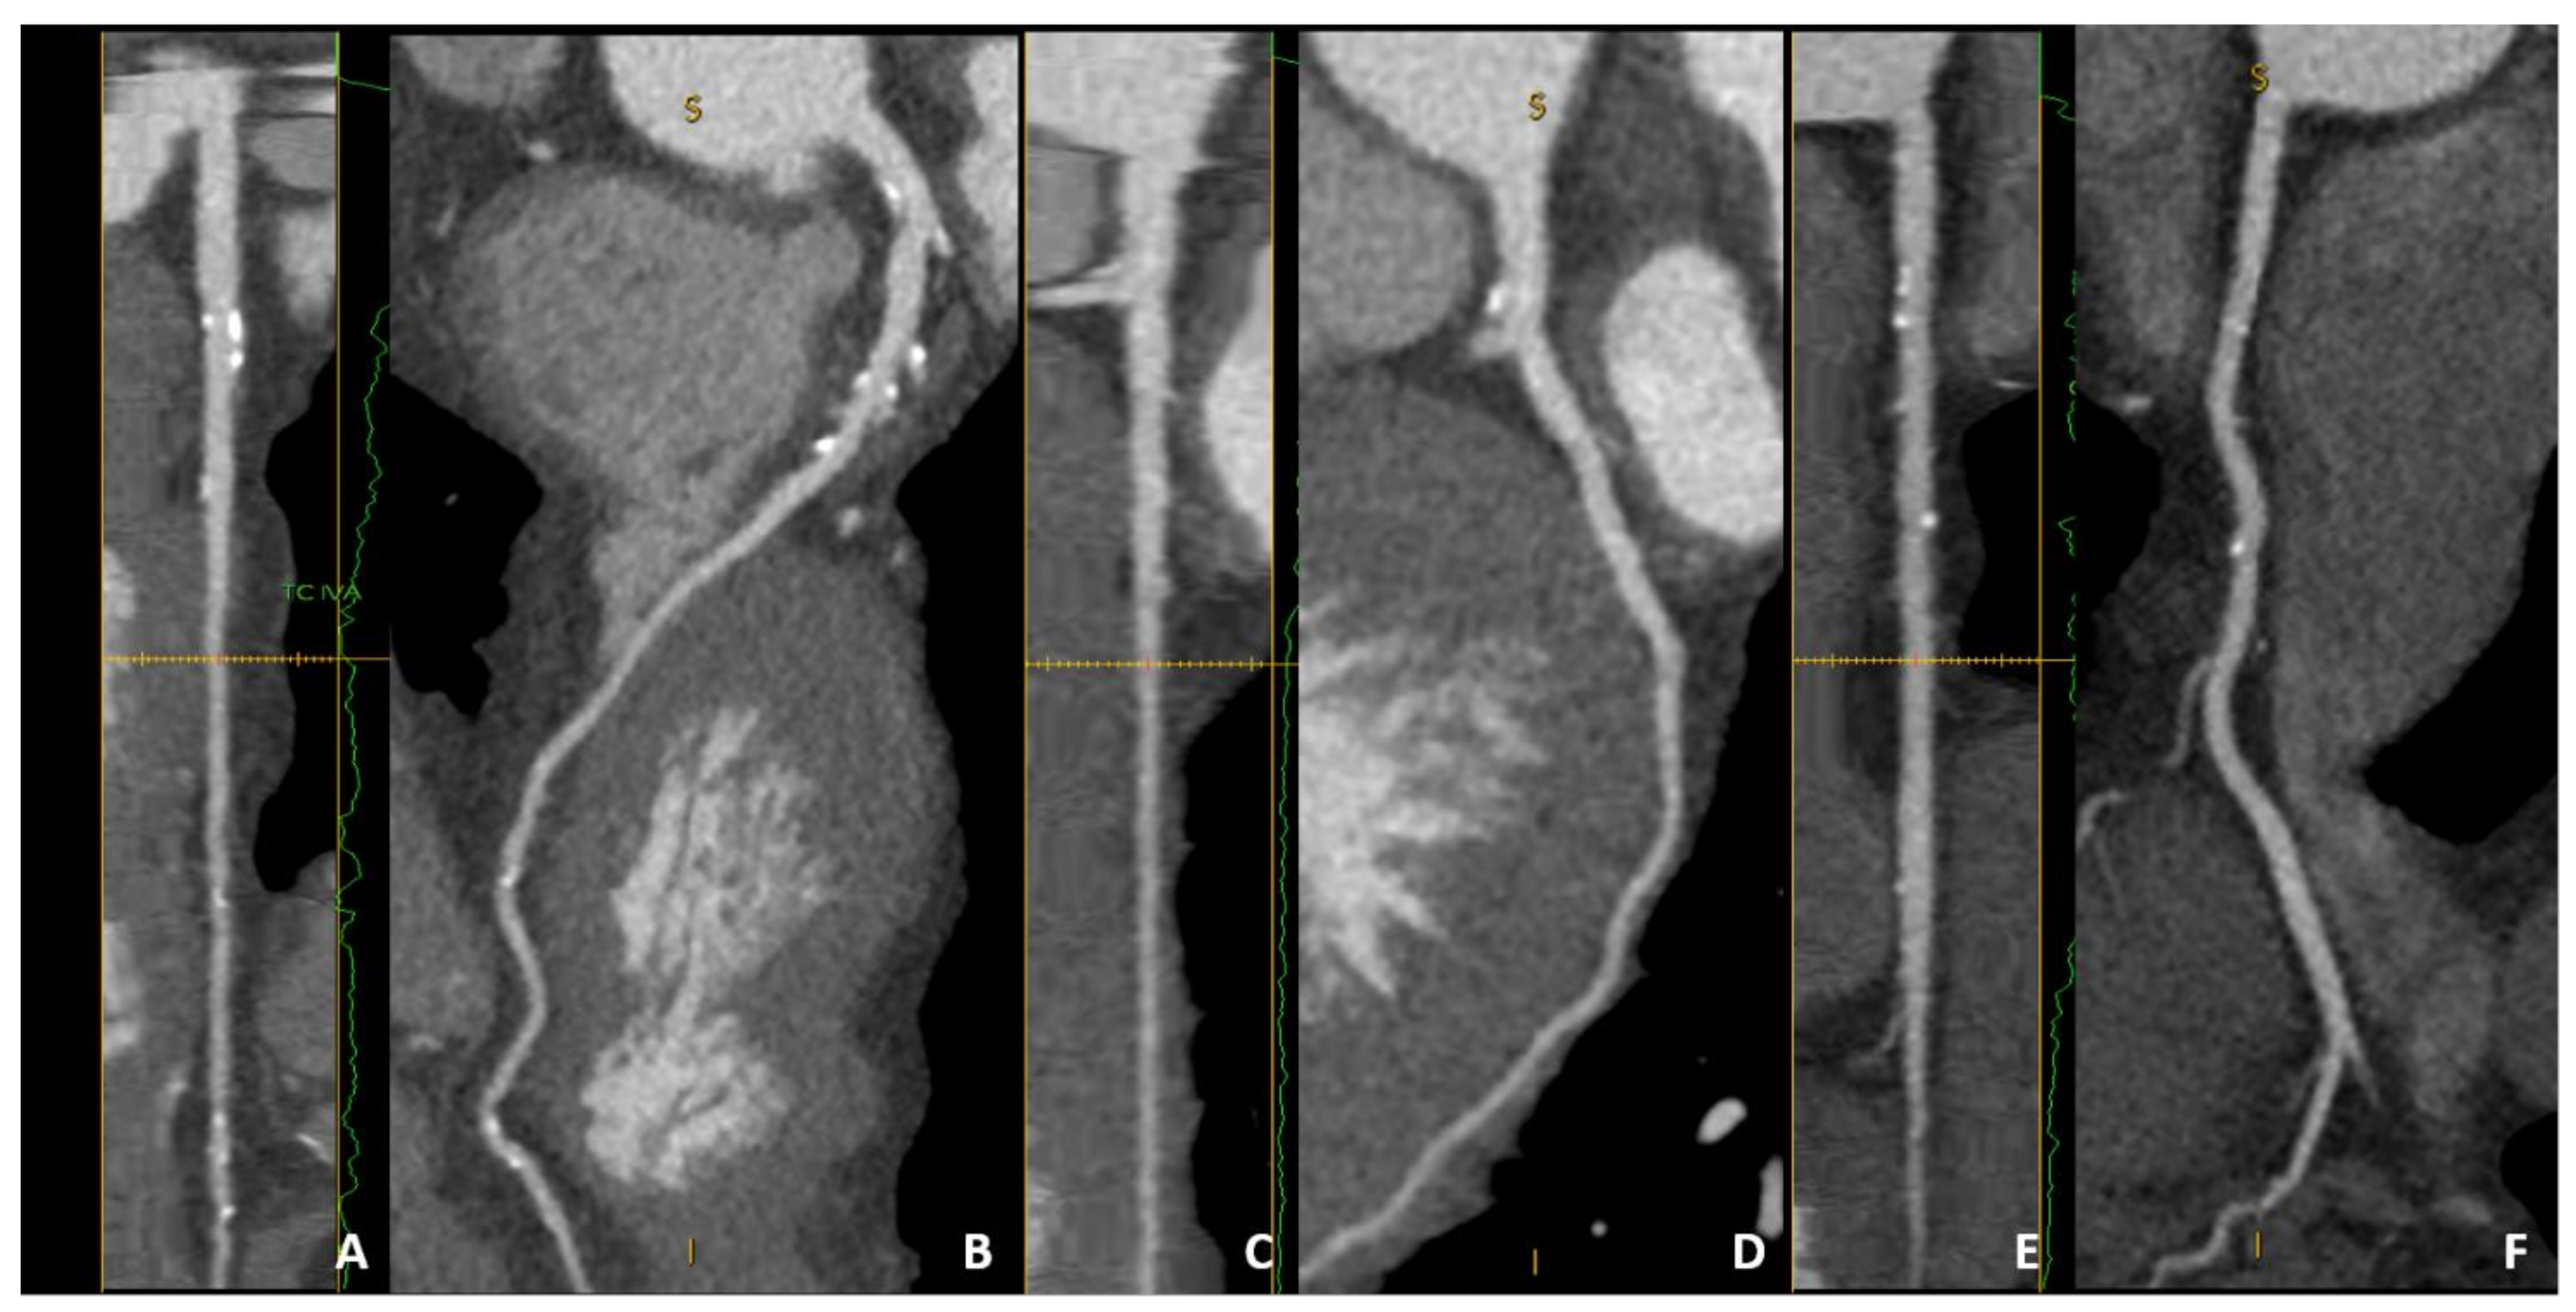

| Patient-Based | Segment-Based | ||

| Conventional Reading | Advanced Analysis | Conventional Reading | Advanced Analysis |

|